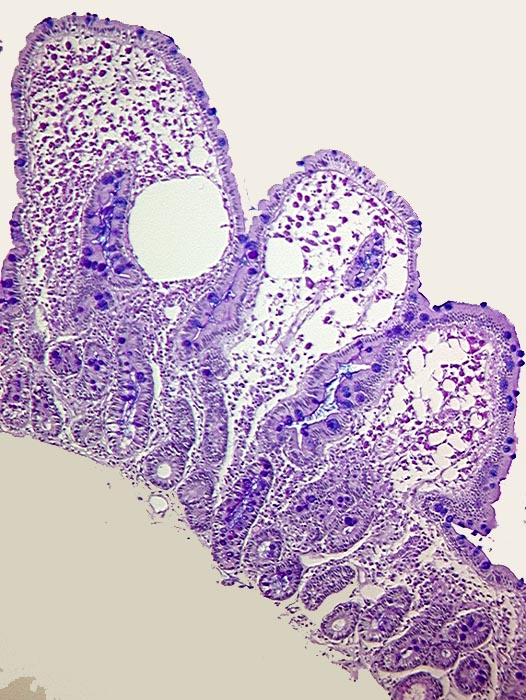

AP/ Morbus Whipple

Morbus Whipple

Entzündung infektiös

Dünndarm

Pathologischer Befund

Normalbefund